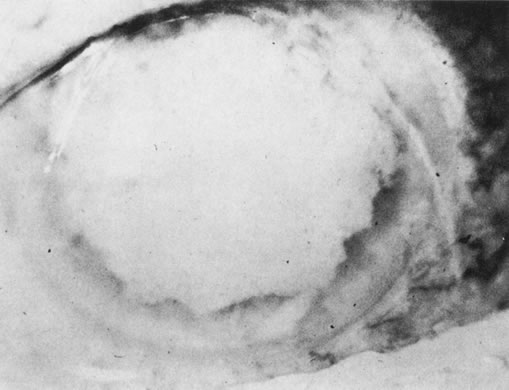

Unfortunately, imaging studies are not always diagnostic. The A- and B-scans shown in Figures 3 and 4 were from a patient with unilateral media opacity referred for evaluation and treatment of a presumed uveal melanoma. Occasionally, if the cataractous lens is scanned tangentially, artifact can occur. A repeat ultrasound at our institution was negative for tumor, and the referral ophthalmologist who performed a cataract extraction noted that no tumor was present and that the patient has an excellent visual outcome. In contrast, the patient shown in Figure 5 was referred with a presumed uveal melanoma with secondary inflammation and a history similar to that described for the patient shown in Figure 111 Ultrasound and CT examinations were not diagnostic. Because the eye was blind and painful, it was enucleated, and an extremely necrotic uveal melanoma was noted histologically. In some necrotic melanomas, the fundus cannot be visualized and the diagnosis cannot be established with imaging studies. Very rarely, a necrotic uveal melanoma can produce sufficient pigment dispersion into the vitreous to obscure the correct diagnosis.12